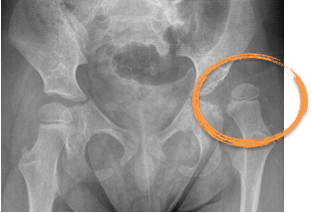

Orthopaedic Complications

Up to 20% of children with CP can lead to musculoskeletal issues such as hip subluxation/ dislocation, scoliosis,and joint deformities due to muscle stiffness or muscle weakness. Physical therapy, pharmacological treatments, orthotic devices or surgical interventions may be required to manage these complications.

Orthopaedic treatments may be necessary to address functional musculoskeletal deformities such as hip subluxation/ dislocation, contractures, scoliosis, or joint deformities.

KKH Hip Surveillance Programme for Children with Long term Neurological Conditions

Special Delivery, Issue 3, March 2018

(By Dr Ng Zhi MIn, Dr Yeo Tong Hong, A/Prof Arjandas Mahadev)

https://www.kkh.com.sg/about-kkh/newsroom/publications/Documents

Special_Delivery_Issue_3_2018.pdf